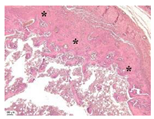

| Point | Type of Microscopy | ||||

|---|---|---|---|---|---|

| Standard Light | Standard Light | Polarization | Standard Light | Phase Contrast | |

| Staining with Hematoxylin–Eosin | Staining with Picrosirius Red | Staining with Picrosirius Red | Staining with Hematoxylin–Eosin | Staining with Hematoxylin–Eosin | |

| 3 | ![]() | ![]() | ![]() | ![]() | ![]() |

| 5 | ![]() | ![]() | ![]() | ![]() | ![]() |

| 8 | ![]() | ![]() | ![]() | ![]() | ![]() |